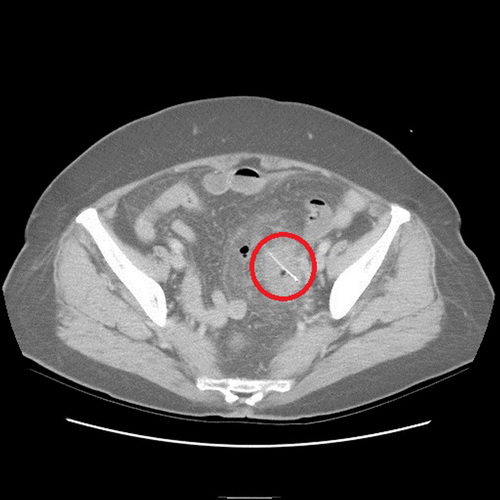

沒想到過了2天,老奶奶又來看診,醫(yī)師便為她安排住院檢查,經計算機斷層檢查,發(fā)現(xiàn)老奶奶乙狀結腸部份竟然有根2.5公分的魚刺,且魚刺已經穿破腸道,導致橫膈膜下方有氣體出現(xiàn),經外科醫(yī)師協(xié)助開刀,終于順利幫老奶奶解決腹部不適的問題。